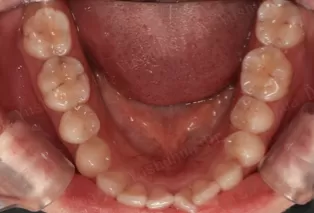

Intraoral photos